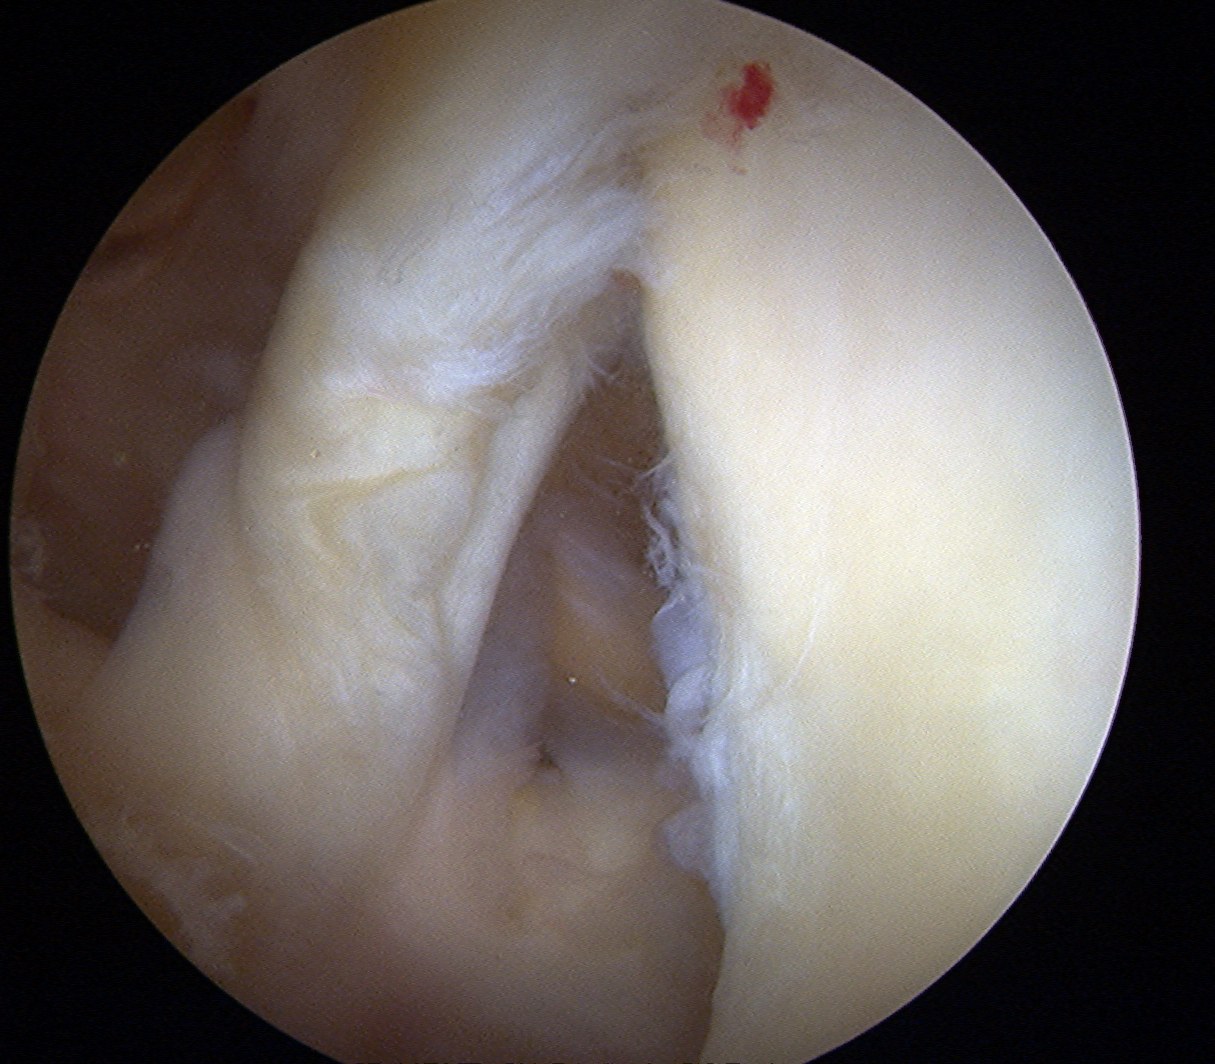

Pass sutures and tie knots

Typically curved suture passers

Aim to tighten capsule medially and superiorly onto glenoid

Shoulder Bankart Repair Suture PasserShoulder Instability inferior Suture passage

Arthroscopy Anterior Bankart RepairShoulder Bankart RepairShoulder Scope Bankart Repair 2